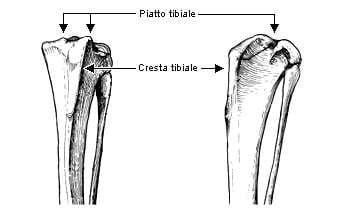

– la parte prossimale (o iniziale) della tibia: si articola solo con il femore, al quale offre due ampie superfici di appoggio, leggermente concave, che complessivamente prendono il nome di piatto tibiale; sulla faccia craniale presenta un’importante protuberanza di forma allungata, detta cresta tibiale, da cui ha origine il legamento rotuleo;